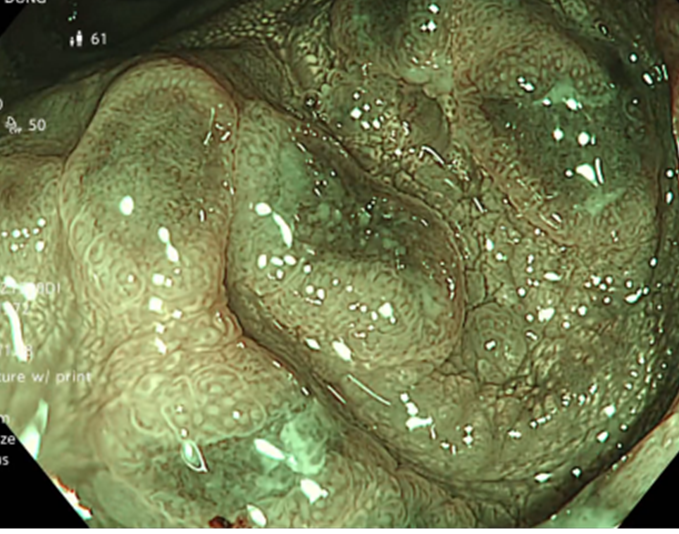

Kết quả nội soi đại tràng: có 3 polyp đại tràng (Paris Is, Kudo IIIL) (đã được cắt polyp qua nội soi), đại tràng sigmoid đã cắt một phần, tổn thương lồi đại trực tràng dạng polyp không cuống, ranh giới rõ, bề mặt màu hồng, có nhiều polyp có lớp nhầy ở trên bề mặt và thấy có hình ảnh da gà xung quanh tổn thương. Trên hình ảnh M-NBI thấy các tổn thương có các tuyến giãn nhẹ nhưng còn đều, mạch máu giãn nhẹ, chưa có biến đổi hình dạng --> đã tiến hành sinh thiết

Hình 2: Hình ảnh nội soi đại tràng

Tổn thương trên nội soi là hình ảnh các tổn thương lồi tại đại trực tràng dạng polyp không cuống, ranh giới rõ, bề mặt màu hồng, có nhiều polyp có lớp nhầy ở trên bề mặt. Chúng tôi nghĩ đến đây là hình ảnh của đa polyp mũ đại tràng mặc dù kết quả mô bệnh học chỉ kết luận là tổn thương viêm trợt mạn tính đang hoạt động, tạo hình ảnh giả polyp. Do trước đó cô ấy đã trải qua nhiều phương pháp điều trị theo hướng viêm ruột như kháng sinh Tinidazol, Levofloxacin, mesalazine… nhưng tình trạng đại tiện nhiều lần không được cải thiện, cùng với đó chúng tôi ghi nhận thấy có sự hiện diện của vi khuẩn H.pylori ở dạ dày. Vì vậy chúng tôi đã quyết định điều trị diệt trừ vi khuẩn H.pylori bằng phác đồ 4 thuốc: Tetracyclin 2g/ngày, Tinidazol 1,5g/ngày, Esomeprazol 80 mg/ngày, Bismuth 480 mg/ngày, thời gian điều trị là 2 tuần.